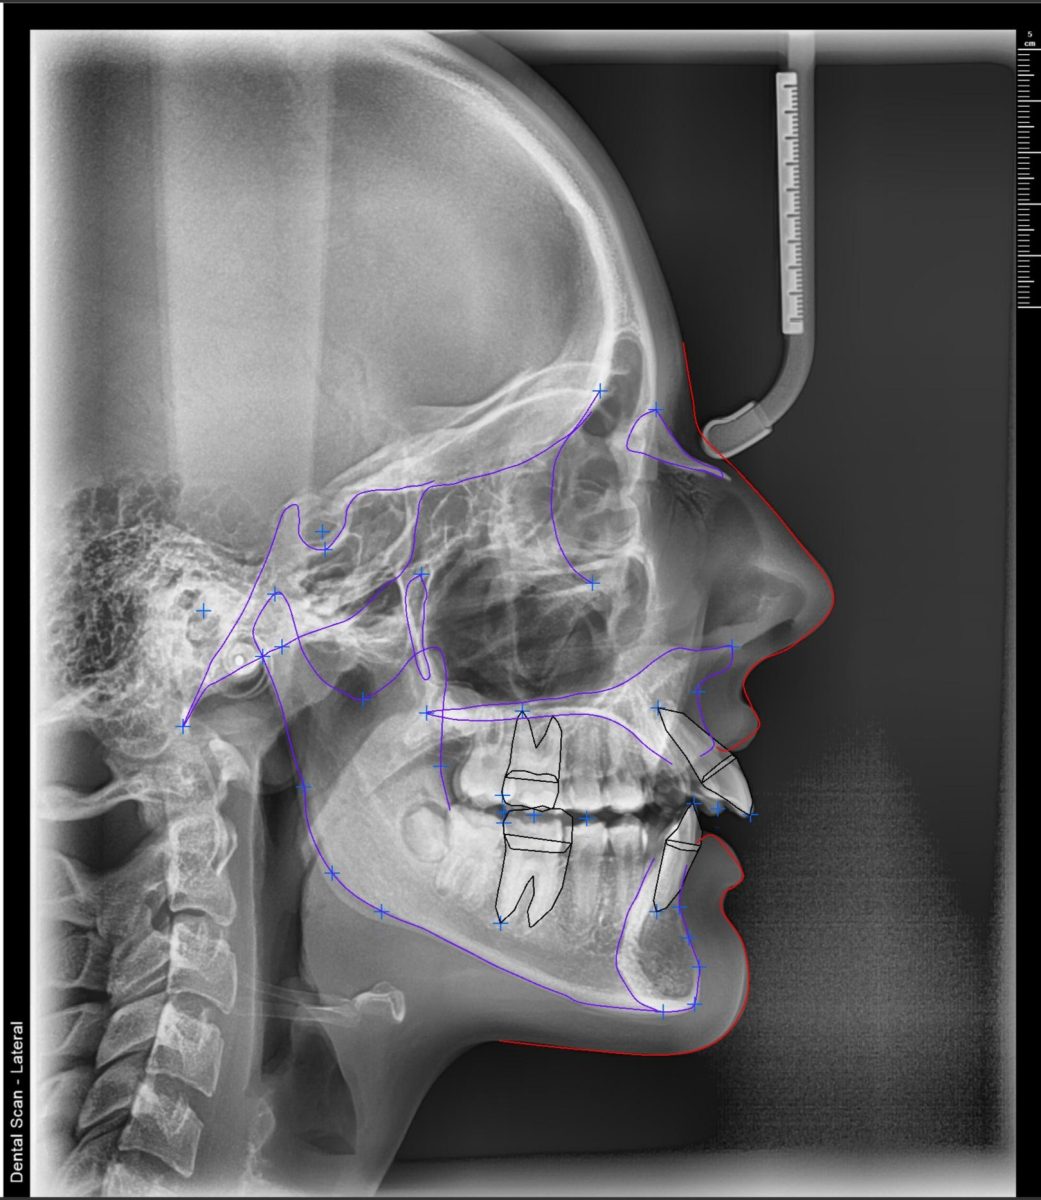

Telerendgen uz pomoć veštačke inteligencije – 15 analiza za 5 minuta

U našem Dental Scan centru, svaki telerendgen snimak se digitalno obrađuje pomoću softvera zasnovanog na veštačkoj inteligenciji.

AI tehnologija automatski prepoznaje cefalometrijske tačke na telerendgen snimku, čime se eliminiše manuelno obeležavanje i smanjuje mogućnost greške u ortodontskoj analizi.

Na osnovu jednog telerendgen snimka, moguće je digitalno izraditi do 15 ortodontskih analiza u roku od svega nekoliko minuta, uključujući:

Zahvaljujući digitalnoj obradi, telerendgen snimak postaje pouzdana osnova za planiranje ortodontske terapije i praćenje rezultata tokom vremena.